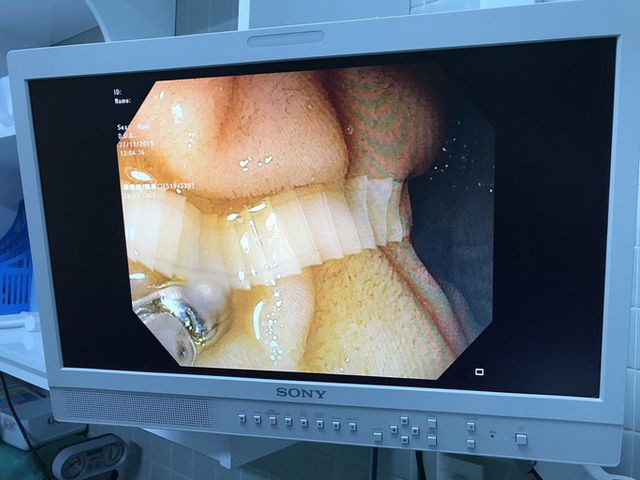

Một con sán đã sống kí sinh trong bụng 1 người đàn ông không biết từ bao giờ mới được lấy ra. ĐƯợc biết ông này có sở thích ăn thịt bò tài ngay từ hồi còn trẻ. Đây có lẽ chính là nguyên nhân xuất hiện con sán này. Một người đàn ông có thói quen ăn bò tái, đã bị nhiễm sán dài hơn 1 m, vừa được các bác sĩ vất vả mới lôi ra hết được

Chiều 2-12, Bệnh viện Chợ Rẫy cho biết vừa thực hiện nội soi gắp một con sán dây bò dài hơn 1 m, trong ruột một bệnh nhân nam 56 tuổi, ở tỉnh Đồng Nai. Nam bệnh nhân đi khám vì khó tiêu nên được chỉ định nội soi tiêu hóa.

Các bác sĩ phát hiện có một con sán dây bò đang trú ngụ trong tá tràng. Tuy nhiên, con sán bám rất chắc nên việc kéo con sán dây ra ngoài rất khó khăn.

Theo BS Tăng Trung Hiếu, Khoa Nội soi Bệnh viện Chợ Rẫy, phải cho bệnh nhân uống thuốc xổ, mới "trục xuất" được con sán dây bò dài hơn 1 m ra ngoài.

"Loại sán này có thể dài từ 2-4 m, ký sinh trong ruột, gây thiếu máu kéo dài, suy dinh dưỡng, rối loạn tiêu hóa, đau bụng cho người bệnh"- BS Hiếu thông tin.

Người đàn ông cho biết mình có thói quen ăn bò tái từ nhỏ, khi ăn chỉ vắt chanh và chế nước sôi vào thịt chứ không nấu chín.